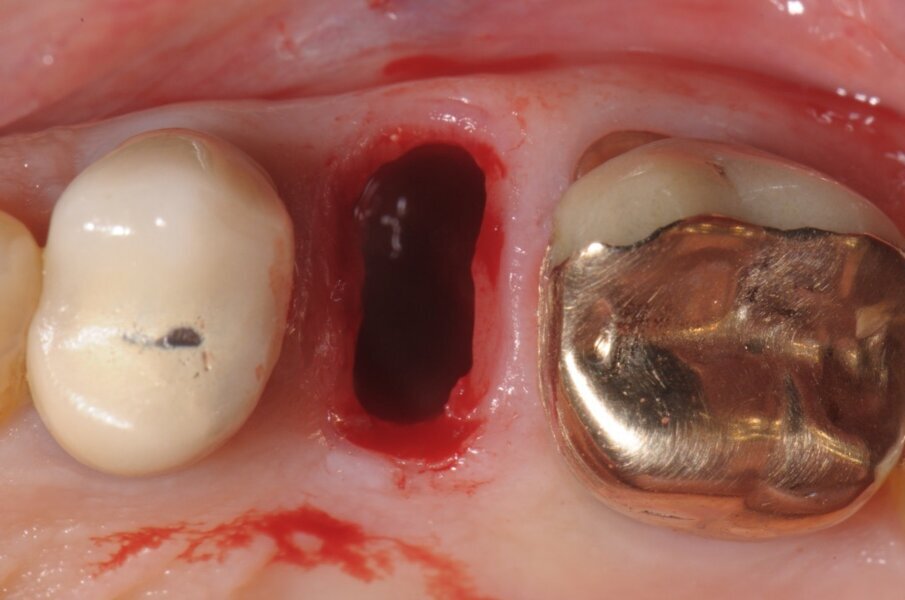

La paziente di 55 anni, non fumatrice, non affetta da alcuna patologia sistemica, da noi trattata con una procedura implantare sostitutiva dell’elemento naturale si era presentata alla nostra osservazione al fine di poter valutare un dolore riferito in sede 2.5 di tipo continuativo tollerabile ma con scarse variazioni di picco algico. L’elemento era stato curato endodonticamente e protesicamente da meno di 1 anno. All’esame obiettivo si presentava una neo protesizzazione individuale su 2.4 e 2.5, mentre su 2.6 si presentava una pregressa protesizzazione in oro-resina con vistosa retrazione gengivale che scopriva un margine corono-protesico impreciso. Il dolore riferito si estendeva tra i 2 premolari in oggetto. Al sondaggio si evidenziava un tragitto patologico di 9 mm in sede mesio-vestibolare della corona in 2.5 (Fig. 1) mentre il sondaggio degli altri elementi si configurava come fisiologico, privo di sanguinamento. L’esame radiografico endorale, mirato al sito ed eseguito con un centratore evidenziava un baffo medicamentale posto mesialmente e associato ad una lacuna ossea adiacente (Fig. 2). La diagnosi di frattura verticale non consentiva alcun recupero radicolare, mentre le radici adiacenti pur avendo delle diafanie periapicali non presentavano sintomi, al fine di un recupero protesico dell’emiarcata si è preferito eseguire una nuova terapia radicolare endodontica (Fig. 3). Fatta la diagnosi si apre un’attenta valutazione sulla tecnica chirurgica, alcune considerazioni vanno fatte sul tipo di estrazione per riuscire ad essere quanto più conservativi, per il mantenimento della cresta ossea vestibolare e per l’architettura gengivale. In tal caso le tecniche atraumatiche prevedono l’utilizzo di strumenti volti alla percussione estrattiva della radice, o al sezionamento obliquo o all’uso di strumenti ultrasonici che lesionano l’attacco dei legamenti parodontali senza intaccare la struttura ossea. Su quest’ultima è ricaduta la nostra tecnica consentendoci di ottenere un sito pulito da frammenti sia ossei che radicolari e riducendo al minimo le lesioni vascolari, senza lembi d’accesso e con un alveolo esangue.

All’ispezione l’alveolo si presentava integro e ben conservato nel perimetro adiacente ai denti limitrofi, la scelta verso l’impianto immediato, nonostante l’evidente mancanza ossea residua oltre apice, che ci avrebbe permesso di ottenere una stabilità primaria apicale è stata comunque svolta grazie a un insieme di fattori concomitanti presenti come: l’uso di un impianto con forma similradicolare con il conseguimento di una stabilità primaria laterale oltre che apicale, pertanto procediamo con il sondaggio di una fresa a diametro crescente sino alla misura voluta che in tal caso era 4.3 mm (Fig. 4). Il taglio verticale delle frese hanno consentito di ottenere un recupero osseo utile per il riempimento di spazi residui. Prima di inserire l’impianto scelto (Conelog 4.3x13 mm-Camlog) procediamo ad ulteriore sondaggio con prova di Valsalva per escludere qualsiasi comunicazione col limitrofo seno mascellare. A procedura ultimata e a impianto inserito, la possibilità è duplice: o chiudere la ferita con un patch mucoso prelevato dal palato4 o posizionare una vite di guarigione sagomata, come nel caso in questione approfittando dello spessore palatino connettivale, prelevare un piccolo patch inserendolo vestibolarmente così da ridurre la morbilità per il paziente stesso e aumentando lo spessore connettivale ai fini estetici (Fig. 5)5.

Fig. 3 - Visione occlusale del sito estrattivo nella fase immediatamente successiva la rimozione radicolare.